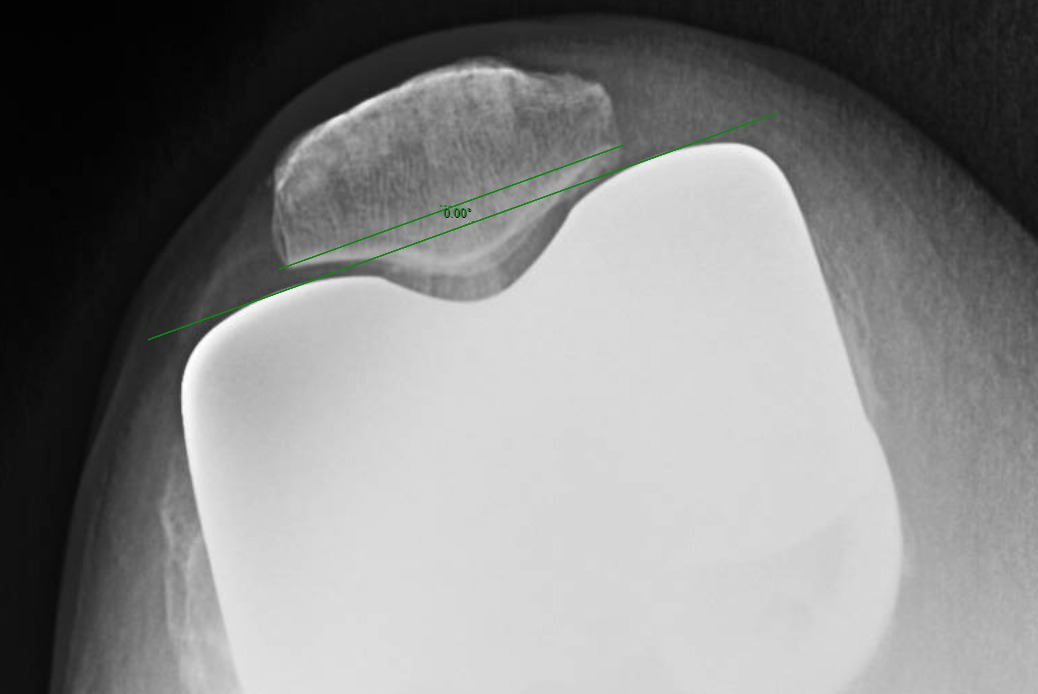

Measurements were performed by one rater following extensive training from the senior author using a standardized measurement protocol. The rater was blinded to the use of robotics when measurements were made. Assessment of postoperative merchant view radiographs on digital imaging software according to the method of Gomes et al. was conducted (Gomes, Bechtold, and Gustilo 1988). The angle between the resected surface of the patella and a line tangent to the anterior condylar axis of the femoral component was measured and recorded (Figures 1-4). The patellar tilt was recorded as positive when the tilt was lateral and was recorded as negative when the tilt was medial. The absolute value of the patellar tilt was used during data analysis as a neutral of 0° was considered the goal for patellar tilt during surgery, and both increasing lateral and medial tilt away from neutral were considered as increasingly imperfect. The percentage of outliers where the patellar tilt exceeded 3 degrees off neutral was also calculated for each group.